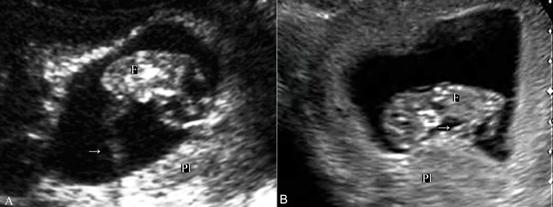

月经后第4周胎盘循环已建立,但经腹超声显像检查要在第7孕周以后、当妊娠囊其他部位的蜕膜反应形成的强回声变薄后才能在妊娠囊一侧显示局限性增厚及密集回声的胎盘。早期的胎盘面积多较大,可以占据子宫腔的1/2~1/3以上;第9孕周~10孕周以后可显示典型的胎盘回声,边缘清晰可认。正常胎盘显示为新月形、弥漫性均匀一致的中等强度回声。胎盘与胎体之间的脐带显示为绳索状回声,漂浮在羊水内。由于脐带较细,多数于早期妊娠过程中常规超声显像检查显示不清,彩色多普勒血流显像检查可以脐带的血流(图2,3)。

图2 早孕期脐带[A:9周胎儿脐带声像图(→); B:11周胎儿脐带回声(→)]